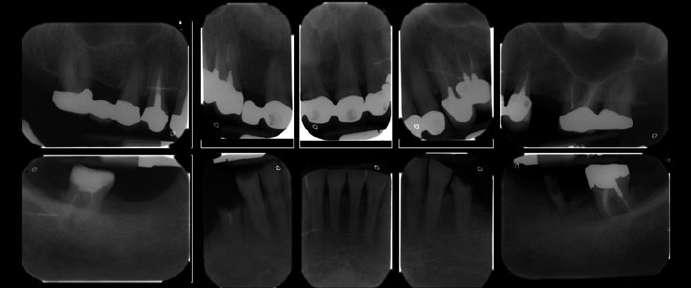

Figura 3. Radiografía inicial del caso donde podemos observar el edentulismo de la paciente y la reabsorción ósea superior e inferior, tras haberse convertido en una paciente edéntula de larga evolución.

Durante la primera consulta, también se realizan varios exámenes instrumentales, como una electromiografía, una radiografía latero-lateral y un conjunto de radiografías intraorales (Fig. 3).

Figura 1. Fotografía del rostro que muestra la pérdida de dimensión vertical y planos estéticos no ideales. Figura 2. Vista intraoral de los arcos. Figura 3. Conjunto de radiografías intraorales que evidencia las zonas edéntulas posteriores mandibulares.